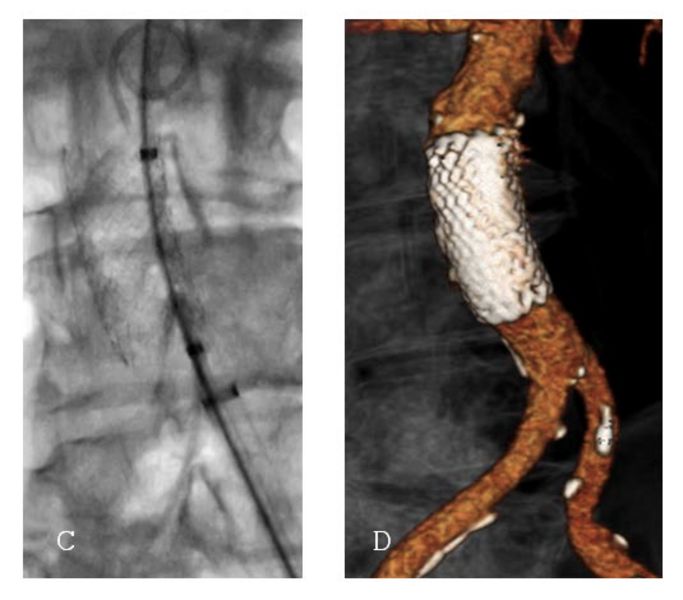

Ein penetrierendes Aortenulkus ist ein Defekt der inneren Gefässwand der Hauptschlagader, verursacht durch Arteriosklerose. Dabei dringt die Gefässverkalkung durch die innere Schicht der Aorta ein und kann zu Aussackungen oder sogar zu einem Riss (Ruptur) führen.Im Gegensatz zu einem Aortenaneurysma, das eine Aufweitung der gesamten Arterie beschreibt, handelt es sich bei einem Aortenulkus um einen lokalisierten Defekt der Gefässwand. Besonders im Bereich unterhalb der Nierenarterien ist diese Erkrankung bisher wenig erforscht.

In der Studie wurden 260 Patientinnen und Patienten zwischen 2018 und 2022 behandelt. Das Durchschnittsalter betrug 74 Jahre, die Mehrheit war männlich. Bei rund drei Vierteln der Patientinnen und Patienten wurde das Aortenulkus zufällig entdeckt, bei einem Viertel hingegen aufgrund akuter Beschwerden wie Bauchschmerzen oder gar einer Ruptur diagnostiziert. Fast alle Patientinnen und Patienten erhielten eine endovaskuläre Therapie, also eine Behandlung über Katheter und Stentprothesen ohne Bauchschnitt. Nur einzelne mussten offen operiert werden.

Die Ergebnisse sind ermutigend: In über 99 % der Fälle konnte die Behandlung technisch erfolgreich abgeschlossen werden, und die Sterblichkeit innerhalb von 30 Tagen lag bei lediglich 1,5 %. Komplikationen waren selten und traten vor allem bei Patientinnen und Patienten auf, die wegen akuter Beschwerden oder einer Ruptur notfallmässig behandelt werden mussten. Begleiterkrankungen wie eine chronische Lungenerkrankung erhöhten ebenfalls das Risiko für Komplikationen.

Die Studie zeigt klar: Die endovaskuläre Versorgung stellt heute den Standard in der Behandlung infrarenaler Aortenulzera dar. Sie bietet eine sichere, schonende und wirksame Therapie – selbst bei komplexen Gefässveränderungen.